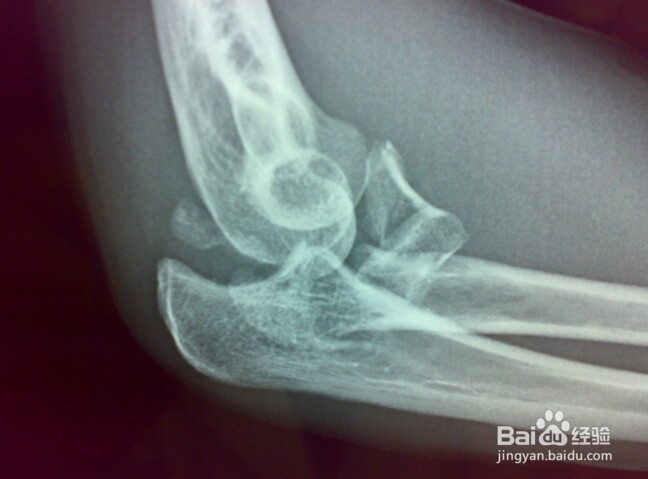

6、X线检查

通过做肘关节的X光片,可以明确诊断。同时X光片还可以对肘关节脱位进行分型并指导复位治疗。